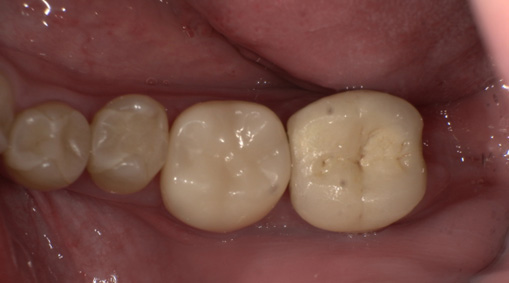

術前・術後の比較

| 術前 | 術後 |

|---|---|

![]() |

9日目 最終的な被せ物をいれます。